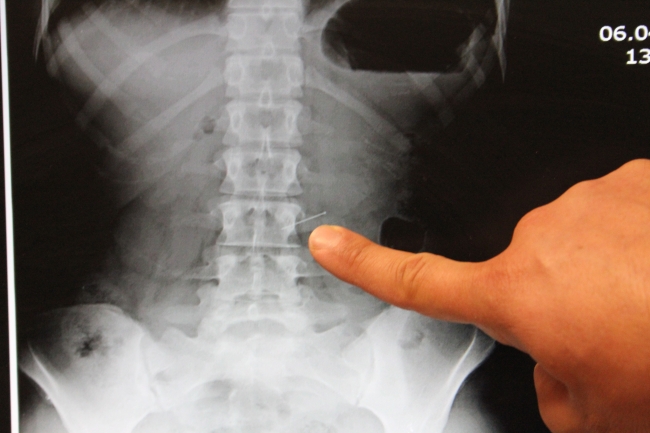

Durumu babasına anlatan Adıgözel, kaldırıldığı hastanede ameliyata alındı. Gerçekleştirilen başarılı operasyonla iğne, Adıgözel'in midesinden çıkarıldı.

Ameliyatı gerçekleştiren Genel Ceraahi Uzmanı Op. Dr. Bülent Erenoğlu, iğnenin 3 saat süren başarılı bir operasyonla mideden çıkarıldığını söyledi.

Bu tür vakalarda, hastaneye vakit kaybetmeden gelinmesi gerektiğini ifade eden Erenoğlu,"Endoskopi yöntemi ile iğneyi başarılı bir şekilde çıkarttık. Tabi midenin dolu olması, midenin çalışması anlamına geliyor. Dolayısıyla iğne midede bir kaç yeri zedelemiş. Fakat şu anda hastamızın bir sıkıntısı yok. Gözlem amaçlı yatırdık. Taburcu etmeyi düşünüyoruz." dedi.